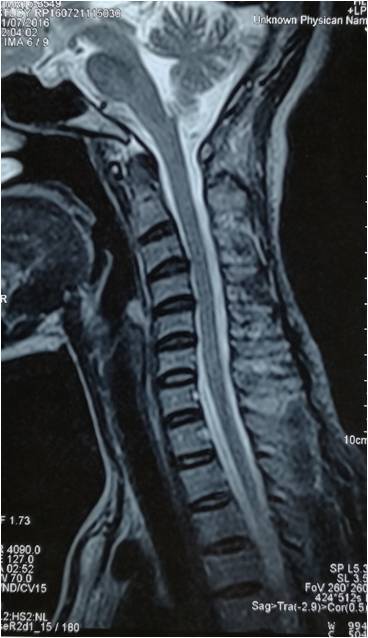

· 颈椎曲度反弓只是提示局部地方有退变,需要根据具体的症状做相应的处理。 如果是伴随颈部的地方疼痛和僵硬,可以选择按摩和热敷;另外就是可以选择药物比如替扎尼定,还可以选择一些膏药比如消痛贴膏有助于缓解。 如果是伴随上肢的麻木等不舒服,那么还可能是压迫了神经根,最好是完善颈部的磁共振检查,可以更为准确的判断病情。 平时要注意个人 · 知道颈椎反弓的成因,接着对因下药。 如果已经颈椎反弓了,可以适当地做一些牵引治疗。 如果病情较轻,通常采用坐位牵引,除此之外,还可以使用卧位牵引,可以在专业人士的指导下适当地借助一些工具,牵引的过程中,要注重牵引的强度,角度,时间以及重量。1510 · 颈椎反弓 一种常见颈椎病。颈椎有正常的生理弯曲,如果没有生理弯曲,甚至向相反的方向弯曲,称为反弓。 人类属于高级脊椎动物,颈椎"c"形向前的生理弧线保证了颈椎活动的高度灵活性,但人们常常发生违背颈椎生理曲线的姿态和活动。

颈椎反弓怎么办-核心提示:颈椎反弓是怎么一回事呢? 颈椎反弓怎么办? 好好的颈椎"说反就反",患者面对颈椎反弓可不能大意! 下文将带你了解颈椎反弓的"那些事",让你"心中有数"。 颈椎是个"磨人的小妖精",不仅容易劳累酸痛,还可能"造反"。 现在的人对于自己的身体 健康 都是十分重视的,都养成了定期去医院检查的好习惯,有些人在一次检查中发现的颈椎反弓 · 五、产生颈椎反弓了怎么办? 康复保守治疗。产生颈椎反弓的朋友不必过于慌张,90%颈椎反弓的患者可以通过康复治疗减轻甚至消除不良症状,改善颈椎曲度。 1、理疗 传统的颈椎牵引、超短波、干扰电等理疗方式于炎症的消除、疼痛的控制有一定作用。此外

· 产生颈椎反弓的朋友不必过于慌张,90%颈椎反弓的患者可以通过康复治疗减轻甚至消除不良症状,改善颈椎曲度。 1、理疗 :传统的颈椎牵引、超短波、干扰电等理疗方式于炎症的消除、疼痛的控制有一定作用。

颈椎生理曲度变直甚至反弓针刀如何治疗